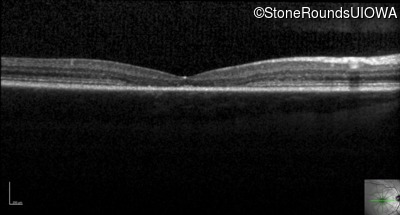

Optical Coherence Tomography - Left - 20/80

Exemplar / OCT Stack